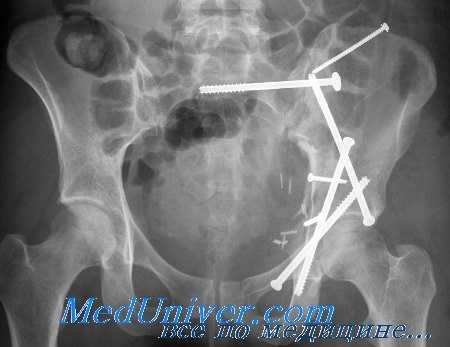

(Слева) На рисунке в проекции входа в малый таз показана травма вследствие ПЗК. Крестцовоостистая, крестцово-бугорковая и крестцово-подвздошная свяжи не повреждены. В этом случае визуализируются двусторонние переломы ветвей лобковой кости. В других случаях может определяться расширение лобкового симфиза, но всегда (Справа) На рисунке в проекции входа в малый таз показана травма связок ПЗК III с отсутствием перелома, отклонение оси кости в области лобкового симфизам, а также полный разрыв ипсилатерального крестцово-подвздошного сочленения, крестцово-остистой и крестцово-бугорковой связок. (Слева) На рисунке в проекции входа в малый таз показана травма ЛК II. Определяется косой перелом лобковой кости и ипсилатеральный задний перелом подвздошной кости со смещением (полулунный перелом). Крестцово-бугорковая и крестцово-остистая связки не повреждены.

(Справа) На рисунке в передне-задней проекции показана травма по типу ВТ с двусторонними переломами ветвей лобковой кости. Правое крестцово-подвздошное сочленение полностью разорвано как кпереди, так и кзади. Такую травму можно обычно отличить от травмы по типу ПЗК по наличию вертикального смещения половины таза. (Слева) КТ-топограмма, передне-задняя проекция: определяется разрыв правого крестцово-подвздошного сочленения как спереди, так и сзади и переломы ветвей лобковой кости. Вертикальное смещение правой половины таза свидетельствует о травме по типу ВТ.

(Справа) КТ, 3D реконструкция: определяется травма по типу ЛК I с вколоченными переломами левой ветви лобковой кости слева и крыла крестца слева в дополнение к сопутствующему перелому правой подвздошной кости. Перелом подвздошной кости не является частью тазового кольца в этом конкретном случае.